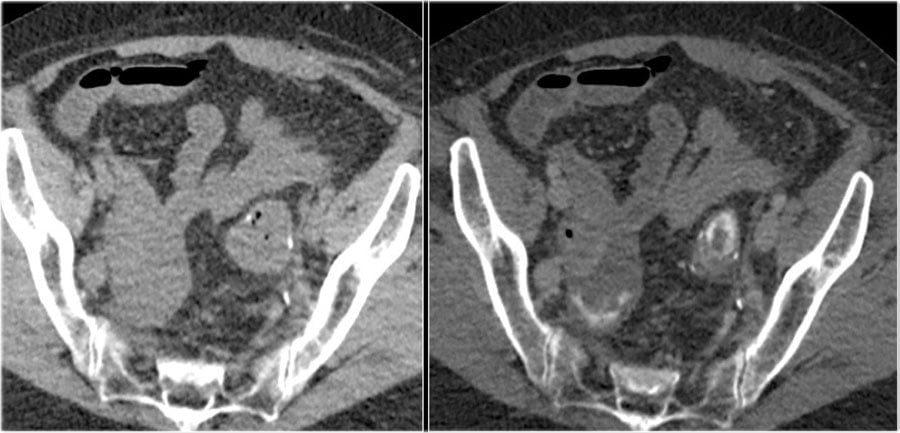

Here a patient with an anastomosis in the lower abdomen after resection of a sigmoid carcinoma.

Compare the NECT without oral or rectal contrast on the left with the images on the right after rectal contrast.

There is no doubt, that contrast in the fluid collection in the right lower abdomen is the result of leakage from the bowel (arrow).

Bệnh nhân bị rò mối nối sau mổ ung thư đại tràng sigma.

Hình bên trái không bơm thuốc so sánh với hình bên phải có bơm thuốc đường trực tràng.

Không còn nghi ngờ gì nữa, có thuốc cản quang trong vùng tụ dịch ở vùng bụng dưới bên phải là kết quả của sự rò từ ruột (mũi tên).